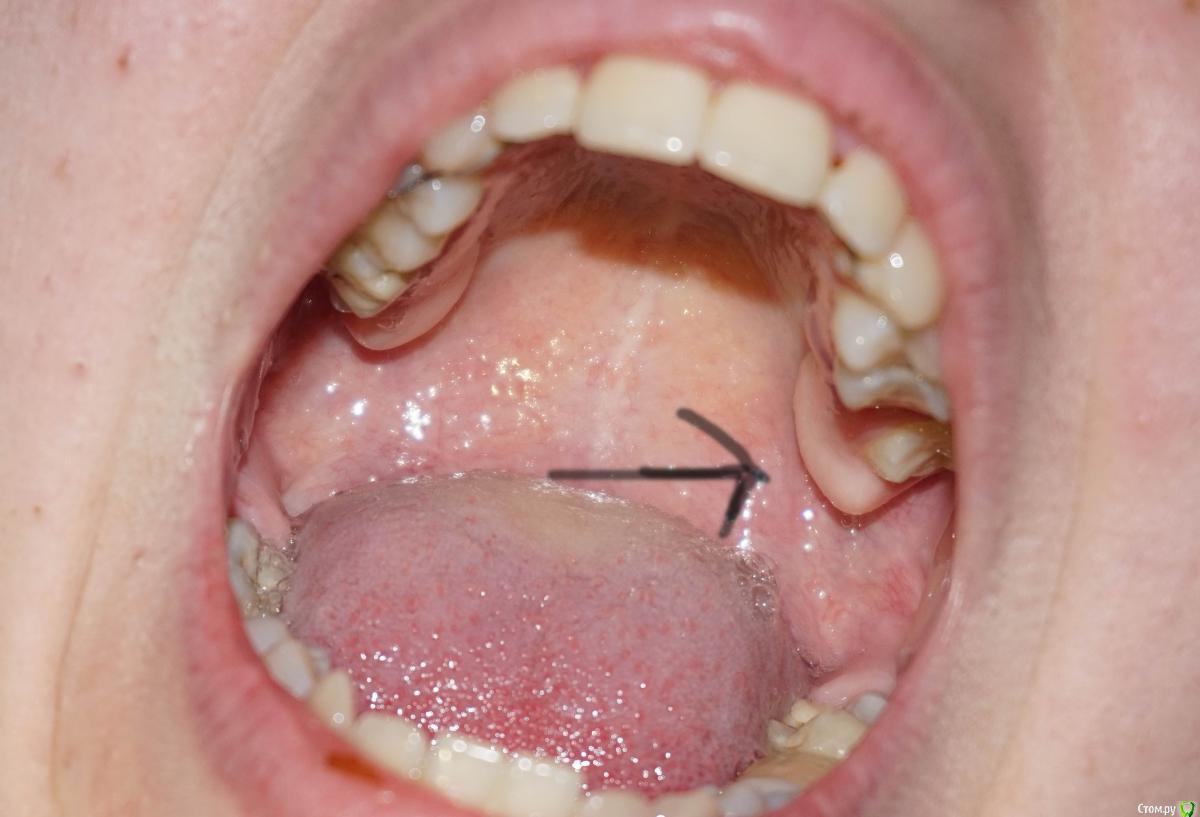

Здравствуйте, помогите, пожалуйста, с консультацией.(фото ниже) Два дня назад произошло небольшое воспаление десны на верхней челюсти.Боли нет, только при расшатывании кусочка зуба, есть припухлость, еще беспокоит увеличение кости.Не дай Бог, зуб мудрости, очень боюсь этой операции.

не о том беспокоитесь...

Сделайте и  выкладывайте панорамный рентгеновский снимок.